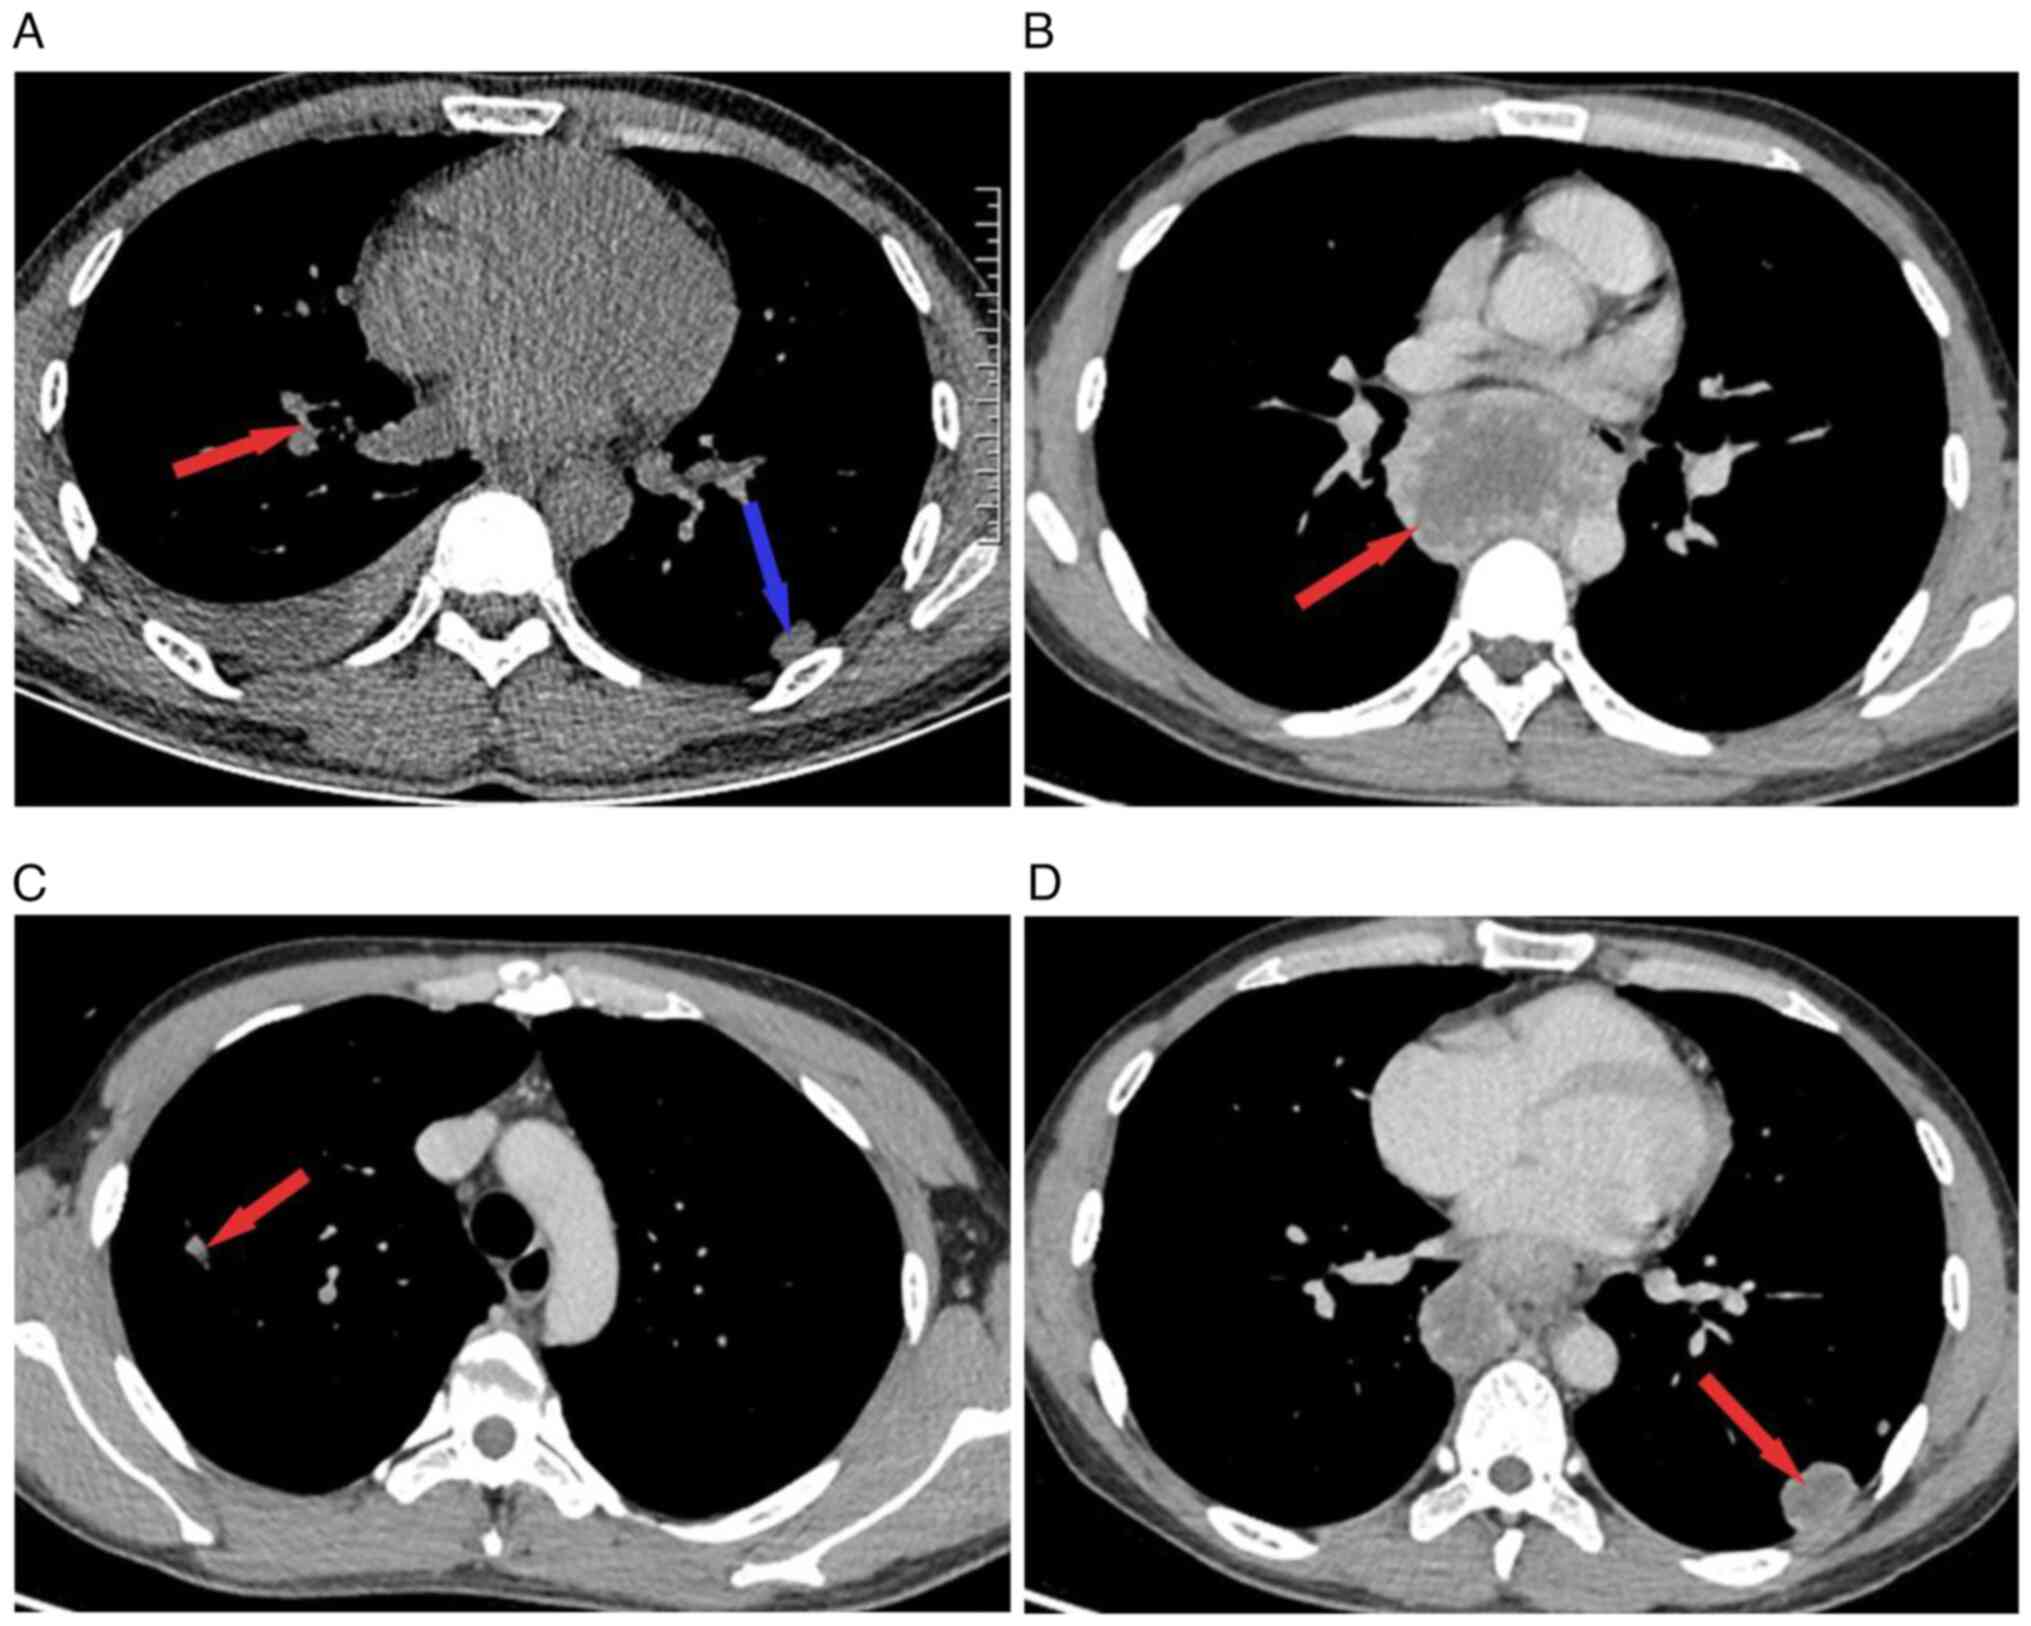

A 27-year-old male was admitted to Taihe Hospital (Shiyan, China) in September 2023 due to intermittent chest and abdominal discomfort for 20 days. 20 days prior to the presentation at Taihe Hospital, the patient presented with unexplained chest and abdominal pain and was admitted to the Department of Gastrointestinal Surgery at a local hospital, where the patient was diagnosed with ‘ileocecal inflammation and pleural effusion’. A chest computed tomography (CT) scan performed at the beginning of September, 2023, revealed nodules in the right upper lung and left lower lung (Fig. 1A). During the hospitalization, the patient received anti-infection treatment and was discharged after the condition improved. However, the patient continued to experience intermittent sternal and epigastric discomfort outside the hospital, accompanied by nausea and anorexia. The patient developed fever 5 days later, with a temperature of ~38˚C, accompanied by a dry cough and no other symptoms. The patient denied a history of smoking or drinking.

Figure 1

The changes of chest CT during September on mediastinal window. (A) Chest CT scan showing a 1.6x0.8-cm nodule in the right upper lobe (red arrow) and a 1.9x1.2-cm nodule in the left inferior lobe (blue arrow), with pleural effusion in the right lung. (B) Chest CT indicating an edge enhancement obvious and huge mass ~6.5x5.1x6.9-cm in the posterior mediastinal. (C and D) Chest CT showing multiple nodules of varying sizes in the upper and lower lobes of both lungs and the larger ones measuring ~2.5x1.8-cm in the lower lobe of the left lung. The pleural effusion disappeared. CT, computed tomography.

In September, 2023, contrast-enhanced CT revealed enlarged posterior mediastinal lymph nodes and multiple enlarged mediastinal lymph nodes (Fig. 1B). Moreover, there were multiple lesions in both lungs (Fig. 1C and D). Compared with the chest CT performed at the other hospital, the number of lung nodules had increased and the mediastinal lymph nodes were markedly enlarged, but the pleural effusion had disappeared. Laboratory examination revealed the following results: whole blood leukocytes, 5.72x109/l [neutrophils, 75.9% (normal range, 40-75%); lymphocytes, 16.3% (normal range, 20-50%); red blood cells, 4.30x1012/l (normal range, 4.3-5.8x 1012/l); platelets, 233x109/l (normal range, 125-135x109/l)]; hs-CRP, 88.03 mg/l (normal range, 0-10 mg/l); NSE, 17.5 ng/ml (normal range, 0-16.3 ng/ml); IL-6, 25.3 pg/ml (normal range, 0-6.6 pg/ml); ESR, 24 mm/h (normal range, 0-15 mm/h); and CEA (normal range, 0-4.7 ug/l) and PCT (normal range, <0.5 ng/ml).